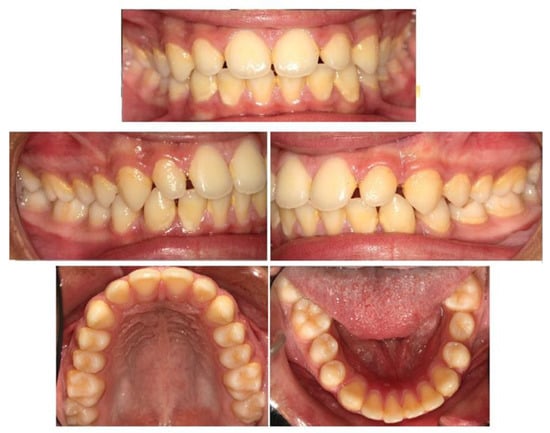

2. Materials and Methods

3. Results